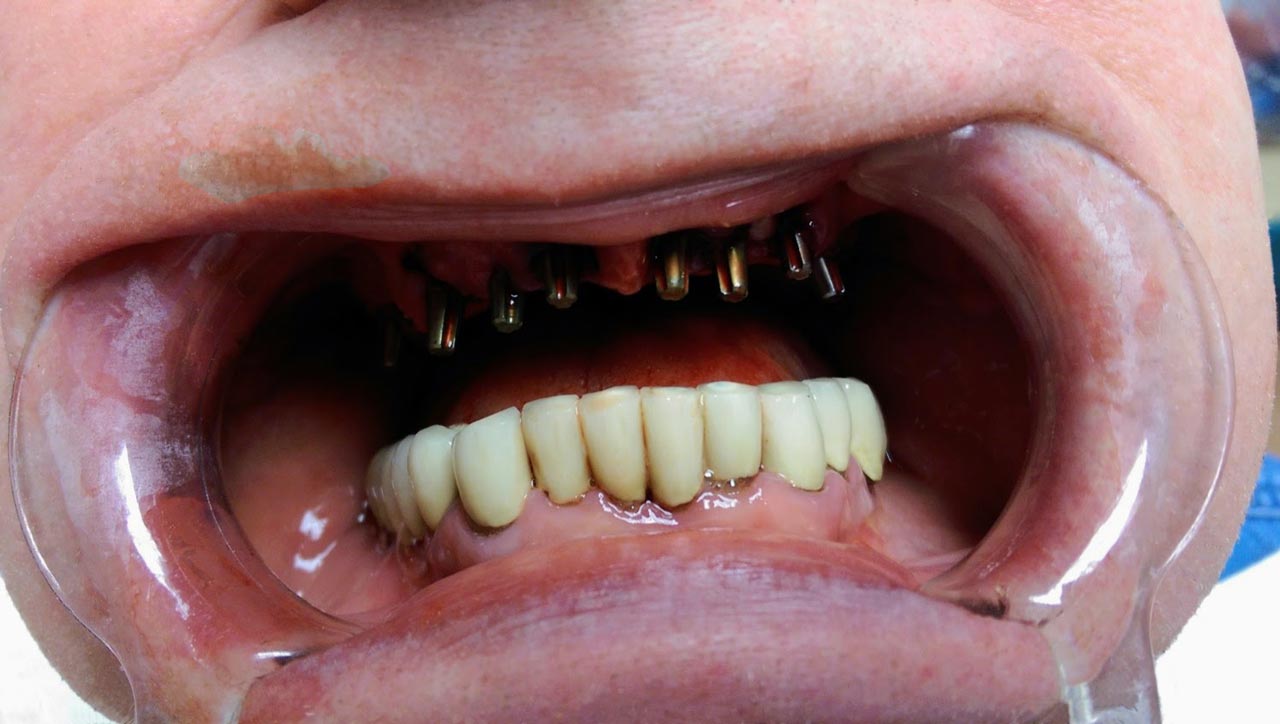

• esettanulmany-08

Műtét másnapján, implantátumok a szájban.